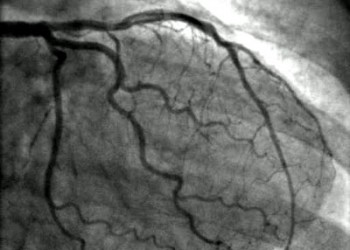

Angină pectorală cu coronarografie normală

O coronarografie normal? nu ne spune decât c? lumenul arterelor coronare epicardice este permeabil ?i c? exist? un flux coronarian bun. Nu putem infirma îns? coronaropatia doar pe baza aspectului normal al angiografiei coronariene.